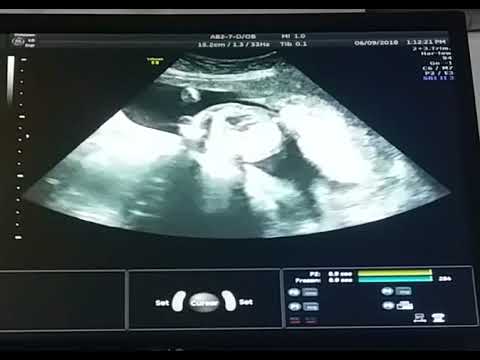

23 недели видео

23 недели видео 113 фотографий